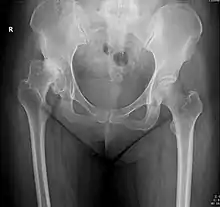

X-ray of the hips of a 40-year-old female, with dysplasia of her right hip.

In the adult hip there are important landmarks to be recognized on plain film radiographs:[3]

Crowe classification

In 1979 Dr. John F. Crowe et al. proposed a classification to define the degree of malformation and dislocation. Grouped from least severe Crowe I dysplasia to most severe Crowe IV.[13] This classification is very useful for studying treatment results.

Rather than using the Wiberg angle because it makes it difficult to quantify the degree of dislocation they used 3 key elements to determine the degree of subluxation: A reference line at the lower rim of the "teardrop", junction between the femoral head and neck of the respective joint and the height of the pelvis (vertical measurement). They studied anteroposterior pelvic x-rays and drew horizontal lines through the lower rim of a feature called "teardrop". The distance between this line and the middle lines of the junction between femur head and neck gave them a measure of the degree of femur head subluxation. They further established that a "normal" diameter of the femur head measures 20% of the height of the pelvis. If the middle line of the neck-head junction was more than 10% of the pelvis height above the reference line they considered the joint to be more than 50% dislocated.[13]